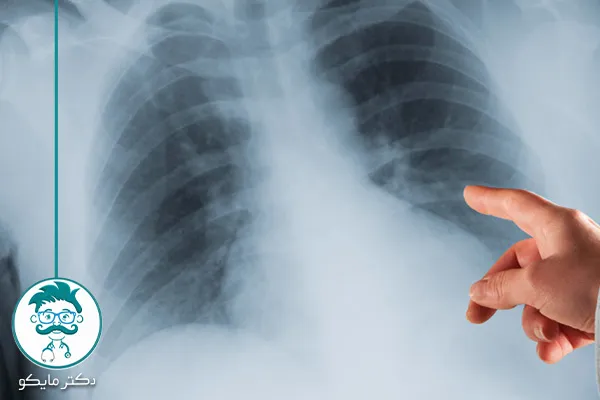

- رادیوگرافی قفسه سینه: اولین قدم برای شناسایی تودههای ریوی.

عکس سرطان ریه خوش خیم

تودههای خوشخیم ریه به ندرت به سرطان تبدیل میشوند و معمولاً به صورت یک توده ی گرد و محدود در تصاویر پزشکی مانند سیتی اسکن یا رادیوگرافی قابل مشاهده هستند. این تودهها به طور کلی تهدیدی برای زندگی فرد نیستند.